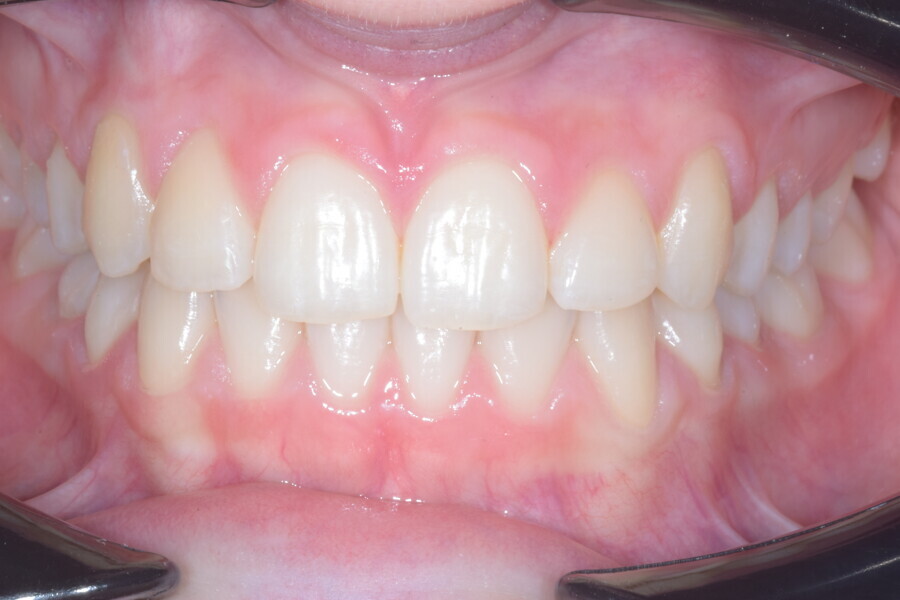

The overall treatment time was 16 months, 11 months of aligner treatment (five months initially for space creation and six months for finalisation after canine eruption) and five months of treatment with MTAs and sectional archwire. At the end of the treatment, a full Class I canine and molar relationship had been obtained, and the impacted canine had fully erupted (Figs. 34–38). A balanced smile with centered midlines had been achieved with an acceptable relationship between the maxillary incisors and lower lip, and torque control of the lateral and posterior segments had generated a broader smile. The limited movement of the upper lip on smiling detected at the beginning was stable, but the smile had improved in terms of expansion and the buccal corridor (Figs. 39–42).

Fig. 39

Fig. 40

Fig. 41

Fig. 42